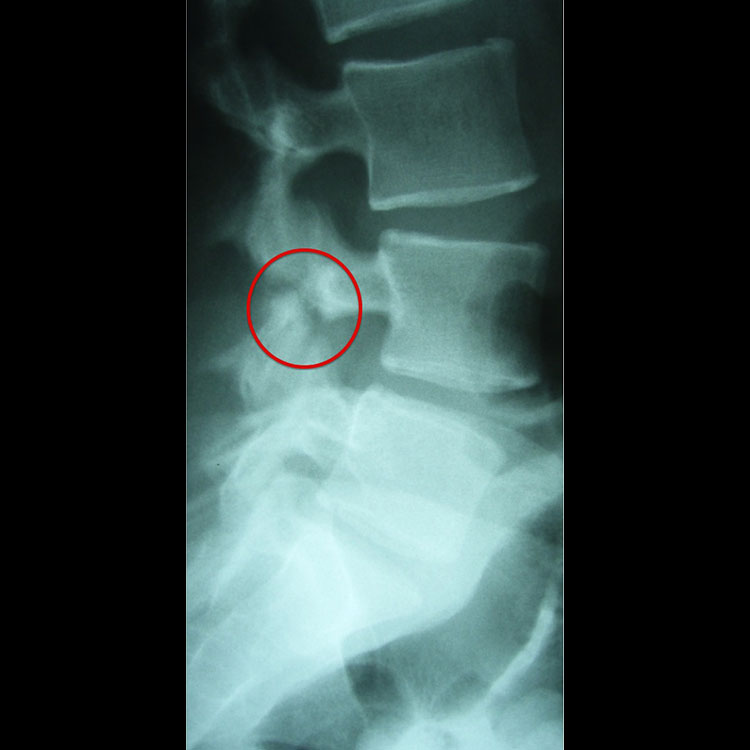

ΑΚΤΙΝΟΓΡΑΦΙΑ

Οι αλλαγές στις ακτίνες Χ ενός κατάγματος λόγω στρες συνήθως συμβαίνουν αργά στην παρουσίαση, αν όχι καθόλου. Σε πολλές περιπτώσεις, τα κατάγματα από στρες δεν αποδεικνύονται ποτέ σε εικόνες ακτίνων Χ. Τα ευρήματα κυμαίνονται από μια πολύ λεπτή περιοχή περιοστικής αντίδρασης έως μια ορατή γραμμή κατάγματος. Οι ακτινογραφίες μπορεί να είναι ένα εργαλείο πρώιμου προσυμπτωματικού ελέγχου για τον αποκλεισμό της ολοκλήρωσης ενός κατάγματος λόγω πίεσης σε ορισμένα οστά που διατρέχουν κίνδυνο, όπως το βασικό πέμπτο μετατάρσιο, ο αυχένας του μηριαίου και το πρόσθιο όριο της κνήμης.

ΣΠΟΝΔΥΛΟΛΥΣΗ

Τα κατάγματα λόγω πίεσης του ισθμου σπονδύλου (σπονδυλόλυση) είναι μια σχετικά συχνή αιτία επίμονου πόνου στη μέση στον νεότερο ποδοσφαιριστή.20 Η περιοχή pars είναι εκείνη η περιοχή του ελάσματος που βρίσκεται κάτω από την κάτω αρθρική απόφυση του σπονδύλου πάνω. Το ίδιο το έλασμα είναι η λεπτή γέφυρα οστού που συνδέει το μίσχο με την ακανθώδη απόφυση. Η σπονδυλολίσθηση είναι η πρόσθια ολίσθηση ενός σπονδυλικού σώματος σε σχέση με τον γειτονικό του σπόνδυλο και αυτό αναπτύσσεται σε περίπου 5% των αθλητών με κατάγματα πίεσης παρ. Είναι συχνότερο σε νεότερες, σκελετικά ανώριμες αθλήτριες και γυναίκες.21

Διερευνήσεις

Οι ακτινογραφίες μπορούν να ανιχνεύσουν χρόνια, πλήρη κατάγματα από το στρες, αλλά δεν θα ανιχνεύσουν οξέα κατάγματα από το στρες. Η μαγνητική τομογραφία είναι γενικά η μέθοδος εκλογής. Οίδημα μυελού των οστών μπορεί να φανεί στην περιοχή pars και μια γραμμή κατάγματος μπορεί να είναι ορατή στην σταθμισμένη εικόνα T1. Μπορεί να απαιτείται στοχευμένη αξονική τομογραφία για τον περαιτέρω χαρακτηρισμό της παρουσίας και της πληρότητας μιας γραμμής κατάγματος. Δεδομένου ότι το οίδημα μυελού των οστών στη μαγνητική τομογραφία μπορεί να διαρκέσει πολύ πέρα από το στάδιο της κλινικής επούλωσης, η σειριακή μαγνητική τομογραφία δεν χρησιμοποιείται για την παρακολούθηση συμπτωματικών ασθενών.

Μερικές εικόνες που δείχνουν τραυματισμούς που αφορούν τον ισθμό των σπονδύλων.